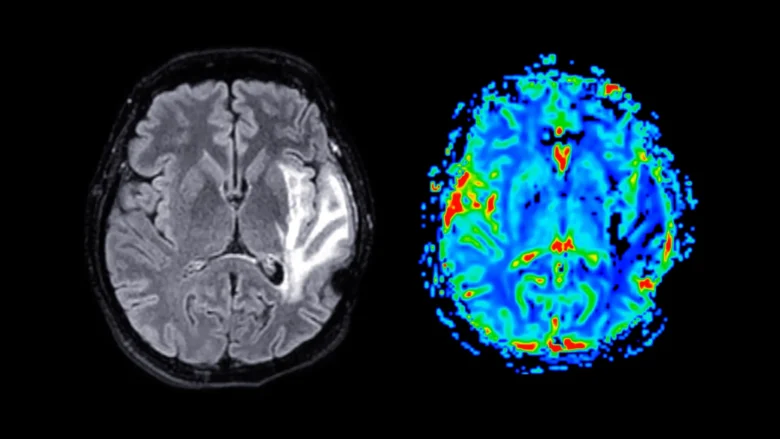

Participants completed questionnaires about menopause symptoms, mental health, sleep patterns, and overall health. Some also completed cognitive tests measuring memory and reaction time. In addition, around 11,000 women underwent magnetic resonance imaging (MRI) scans, which allowed researchers to examine differences in brain structure.

Grey Matter Loss in Brain Regions Linked to Memory and Emotion

Brain imaging revealed that women who were post-menopause showed significant reductions in grey matter volume, regardless of whether they had used HRT. Grey matter contains nerve cell bodies and plays a key role in processing information, controlling movement, and supporting memory and emotional regulation.

The most affected areas included the hippocampus (responsible for forming and storing memories), the entorhinal cortex (the ‘gateway’ for passing information between the hippocampus and the rest of the brain), and the anterior cingulate cortex (part of the brain that helps you manage emotions, make decisions, and focus your attention).